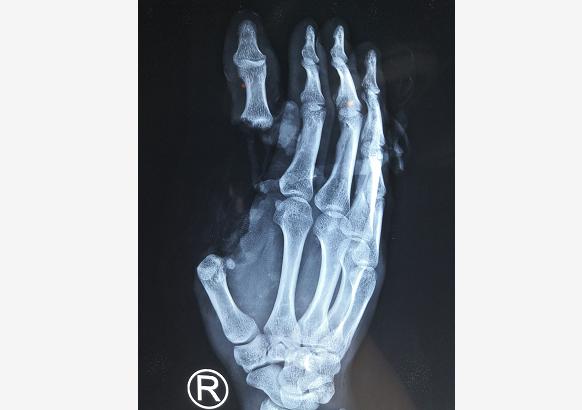

潘医生介绍,小吴的伤势非常严重,到达医院之后,他就被立刻送到手术室准备手术。术中探查发现这是非常严重的旋转撕脱性离断,其拇指伸屈肌腱自肌腹抽出,血管、神经也抽出。面对这个情况,潘医生团队做了一个重大决定,“困难再大,也要一次性解决问题!”“潘医生,难度有些大。”助手惴惴不安地说。“小伙子家庭太困难了,我们必须一次性解决所有问题。”说完,潘医生和助手迅速进入状态,开始这场“硬仗”。

潘医生说,像小吴这种病情,需要2-3次手术。做完拇指再植后,过半年左右再做肌腱转位、神经转位手术。